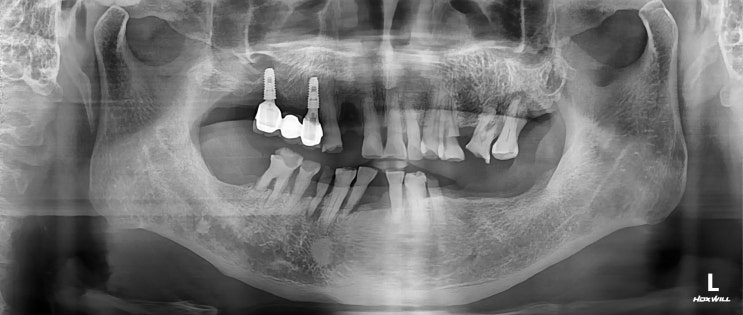

[수서치과] 벌어진 전치부 지르코니아 크라운

안녕하세요 수서역 양심치과 보철과 전문의 수서서울삼성치과 원장 이재현입니다 날이 너무 더워요 낮에 한...